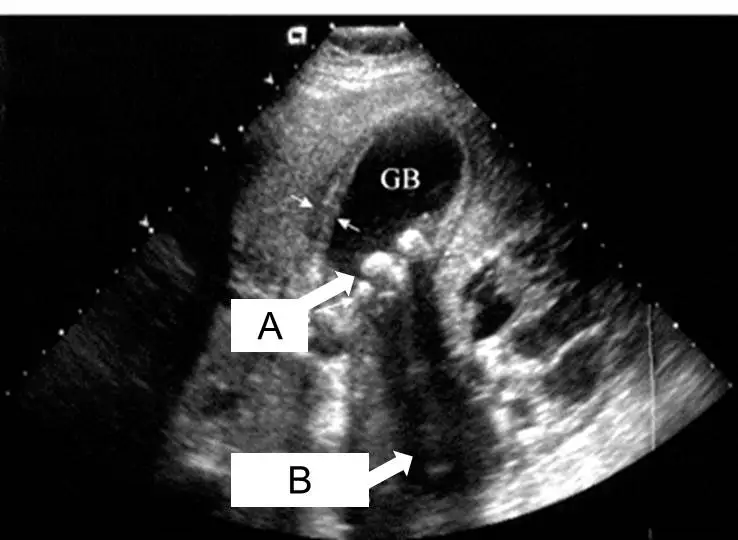

如圖之膽 囊超⾳波 , ⽩⾊箭頭 A及箭頭 B所指可能是何種影像?

AA為膽息⾁, B為⾳影( acoustic shadow )

CA為膽囊結⽯, B為⾳影( acoustic shadow )

本張超音波影像標示「GB」處為膽囊(gallbladder)腔體,呈現典型無回音(anechoic)的暗色液體區域。

箭頭 A(白色箭頭,指向膽囊腔底部):指向一個強回音(hyperechoic)、邊界清楚的病灶,位於膽囊最低處(受重力影響的位置)。此病灶呈現亮白色,為緻密鈣化或結晶性物質(即膽囊結石)的典型表現。膽囊結石因含有膽固醇結晶、膽色素或鈣鹽等成分,對超音波波束產生強烈反射,形成強回音病灶。此病灶具有重力依賴性(gravity-dependent),改變病人體位時位置會隨之移動,可與固著於膽囊壁的膽息肉相鑑別。

箭頭 B(白色箭頭,指向強回音病灶後方):指向位於強回音病灶「正後方」的暗色、均質、帶狀低回音區域。這是典型的音影(acoustic shadow)——超音波波束在遇到強反射或強吸收介質(如結石)時,無法穿透到更深的組織,導致結石後